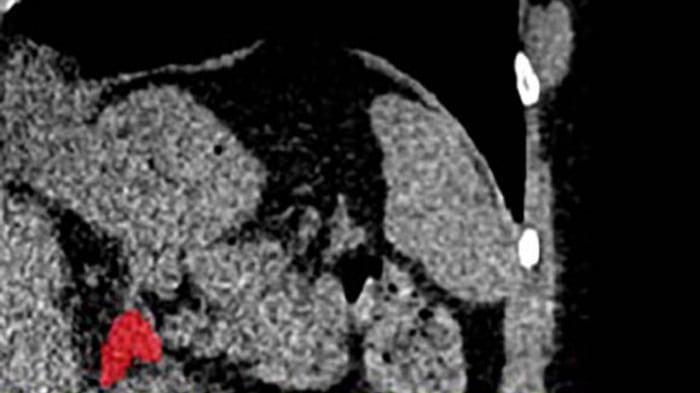

Y es que un equipo de investigadores liderado por la doctora Elena Ghotbi, del Johns Hopkins University School of Medicine, en Estados Unidos, entrenó un modelo de aprendizaje profundo para medir el volumen de las glándulas suprarrenales a partir de tomografías de tórax ya realizadas.

Dado que cada año se realizan decenas de millones de estas tomografías, la técnica tiene el potencial de aplicarse de forma masiva sin necesidad de nuevas pruebas. Gracias a este enfoque, se puede aprovechar información existente para evaluar la ‘carga biológica’ del estrés de forma objetiva.

El indicador, llamado Índice de Volumen Suprarrenal (AVI, por sus siglas en inglés), se define como el volumen de las glándulas suprarrenales dividido por la estatura al cuadrado.